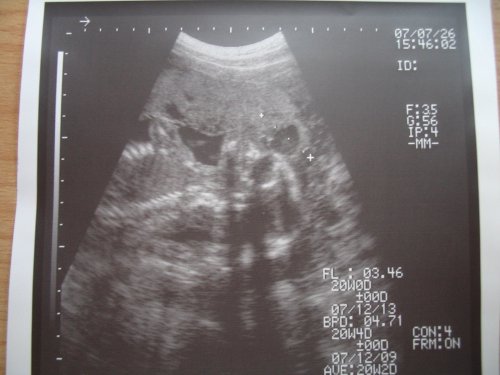

Letím do poradny...dnes mě čeká velký UTZ + monitor srdíčka...